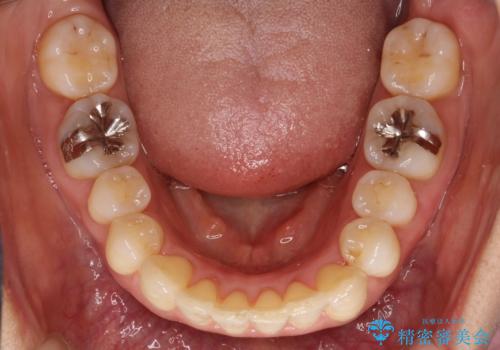

重度のガタガタのインビザラインによる非抜歯矯正

- 上下の歯のガタガタを主訴に来院されました。

インビザラインで奥歯を後方に移動させるのと、歯と歯の間をわずかに削ることでスペースを作り、歯を並べる計画としました。